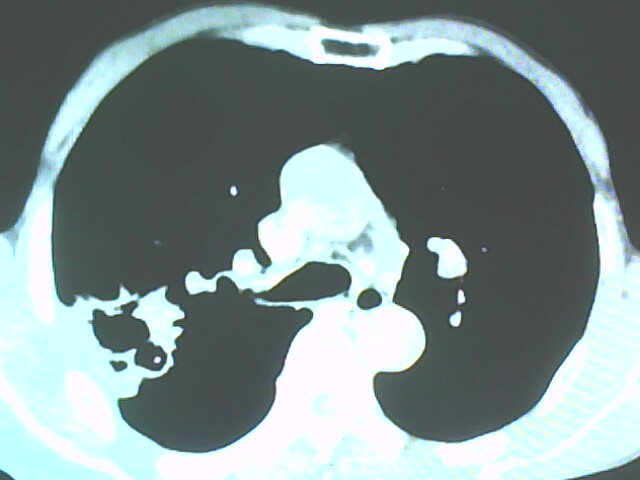

患者,男,66岁,以咳嗽、咳痰伴胸痛来就诊。

胸片提示右上肺占位病变。请各位老师看看ct。

考虑癌性空洞可能性大,空洞内壁不规则,病灶周围模糊,分叶、有毛刺

空洞内壁不规则,病灶周围模糊,分叶、毛刺呈日光放射状,突然截断,支持考虑癌性空洞

考虑右肺上叶后段周围型肺癌并癌性空洞形成。

考虑癌性空洞可能性大,内壁不规则,洞壁薄厚不均呈结节状突起,边缘模糊,分叶,毛刺

右上肺后段肺癌:

典型癌性空洞(偏心性,壁厚薄不均,内壁不光整),周围毛刺较僵硬,且有刺突征和血管聚集征